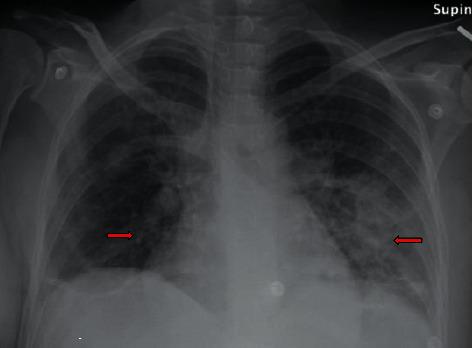

Isolated native pulmonic valve infective endocarditis (IE) is a rare occurrence. The most commonly involved valves in injection drug users are the tricuspid valve followed by mitral and then aortic valves. Most reported cases of methicillin-resistant (MRSA) IE involve multiple valves. Isolated involvement of the pulmonic valve in IE is infrequent, especially in intravenous drug users or patients with indwelling catheters, prosthetic valves, or implantable cardiac devices. Here, we report a young postpartum female patient with isolated native pulmonic valve MRSA IE with MRSA bacteremia and history of active injection drug use. A PubMed literature review revealed a single described prior case report in a postpartum female. The patient's clinical course was complicated by a large native pulmonic valve vegetation, septic pulmonary emboli, pelvic abscess, polyarticular septic arthritis, and clavicular osteomyelitis. The patient underwent bioprosthetic pulmonic valve replacement and finished six weeks of intravenous vancomycin for complete recovery.

摘要

孤立性天然肺动脉瓣感染性心内膜炎(IE)较为罕见。注射吸毒者中最常受累的瓣膜是三尖瓣,其次是二尖瓣和主动脉瓣。大多数报道的耐甲氧西林金黄色葡萄球菌(MRSA)感染性心内膜炎病例累及多个瓣膜。肺动脉瓣在感染性心内膜炎中单独受累的情况并不常见,尤其是在静脉吸毒者或有留置导管、人工瓣膜或植入式心脏装置的患者中。在此,我们报告一名年轻的产后女性患者,患有孤立性天然肺动脉瓣MRSA感染性心内膜炎伴MRSA菌血症,并有活跃的注射吸毒史。一项PubMed文献综述显示,此前仅有一篇关于产后女性病例的报道。患者临床过程复杂,伴有巨大的天然肺动脉瓣赘生物、脓毒性肺栓塞、盆腔脓肿、多关节脓毒性关节炎和锁骨骨髓炎。患者接受了生物人工肺动脉瓣置换术,并完成了六周的静脉注射万古霉素治疗以实现完全康复。